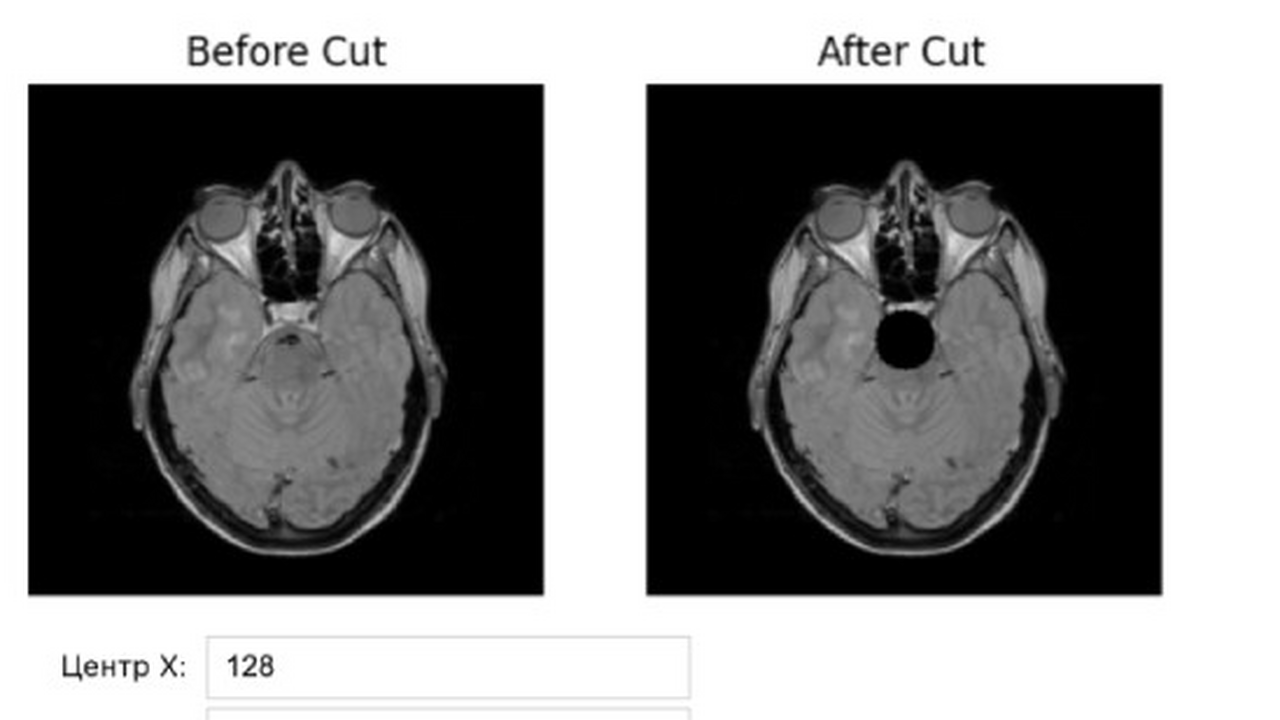

В Самарском политехническом университете магистранты Иван Белов и Егор Бекиш разработали платформу «ДатаСкульпт», которая позволяет создавать синтетические МРТ-снимки головного мозга с помощью искусственного интеллекта. Проект ведёт старший преподаватель Андрей Пенский.

«ДатаСкульпт» решает эту проблему: платформа генерирует снимки с нужной локализацией и выраженностью патологий, а встроенные алгоритмы проверяют качество изображений, обеспечивая их корректность и безопасность.